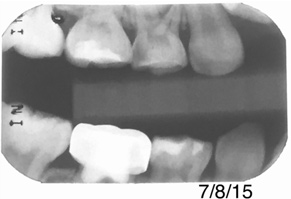

Figure 15 shows bitewings of an 11-year-old boy with high caries risk and history of proximal "kissing lesions" on his primary molars in all four quadrants. He then presented with incipient lesions in his permanent teeth. After resin infiltration (Figure 16), results have been stable for 2 years.

Fig 15. Bitewing of an 11-year-old boy.

Figure 15

Fig 16. Same patient several months later.

Figure 16